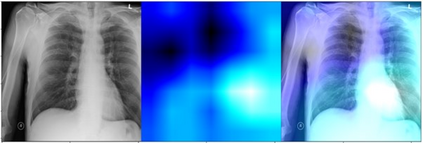

Deep learning (DL) analysis of Chest X-ray (CXR) and Computed tomography (CT) images has garnered a lot of attention in recent times due to the COVID-19 pandemic. Convolutional Neural Networks (CNNs) are well suited for the image analysis tasks when trained on humongous amounts of data. Applications developed for medical image analysis require high sensitivity and precision compared to any other fields. Most of the tools proposed for detection of COVID-19 claims to have high sensitivity and recalls but have failed to generalize and perform when tested on unseen datasets. This encouraged us to develop a CNN model, analyze and understand the performance of it by visualizing the predictions of the model using class activation maps generated using (Gradient-weighted Class Activation Mapping) Grad-CAM technique. This study provides a detailed discussion of the success and failure of the proposed model at an image level. Performance of the model is compared with state-of-the-art DL models and shown to be comparable. The data and code used are available at https://github.com/aleesuss/c19.